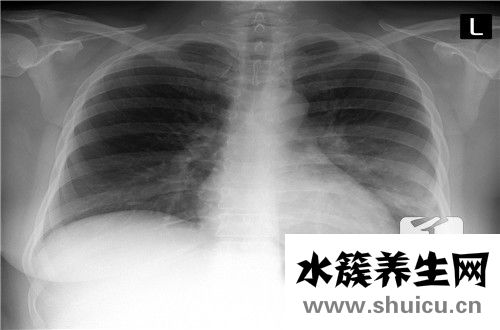

如果你總是感覺肺部有痰在咳嗽,此時你會感到非常不舒服。這時,你可以通過某些方法來促進咳痰。例如,你可以喝更多的熱水,這對幫助咳痰有很好的效果。此外,你應該吃一些能潤肺止咳的食物。這個地區有很...